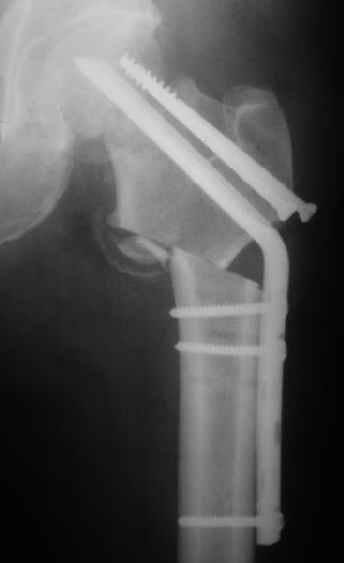

Мужчину 56 лет оперировали у нас в августе 2003 г. - вальгизируюшая остеотомия из-за позднего (через 2 мес. после травмы) поступления с переломом шейки бедра (картинки 1,2). Курильщик, соматической патологии не было. Сейчас поступил с жалобами на проблемы в области тазобедренного сустава, на снимках 3,4 видно вырезывание клинка.Чтоб можно посоветовать в этой ситуации? Заранее спасибо.

A male 56 years old was operated in Aug 2003 - valgus osteotomy performed because of delayed admission with neck fracture (2 months) images 1,2. Smoker, no other major medical problem. Now he re-admitted with the images 3,4.What would you do in the situation?THX in advance.

По-моему, проблема не только в вырезывании клинка, но и в развитии аваскулярного (асептического) некроза головки бедра. Его развитие, кстати, представляется вполне закономерным при предпринятой тактике. Считаю наиболее рациональной тактикой сейчас удаление всех конструкций, реостеотомии (если само не развалится) на прежнем месте и тотальное эндопротезирование с использованием длинной ножки дистальной фиксации с воротником без цемента. Проксимальный фрагмент при этом будет являться аутотрансплантатом, нанизанным на ножку. После операции предписать более щадящий реабилитационный режим (ходьба с костылями месяцев до 4-х).

Сама собой просится идея о тотальном эндопротезировании тазобедренного сустава протезом по типу онкологического (обычный "сажать" уже некуда). Аргументы:

1. Налицо рентгенологическая картина коксартроза. Деформирована головка, суставная щель сужена и т.д.

The osteotomy seems to be showing bony union. (New bone at the medial aspect). There is a big step in the union. The distal fragment is way out laterally.There is overiding of the neck over the head. The screws are out superiorly and the blade also coming out. There is no union of the neck fracture. The head does not seem to be normal- distorted in shape and probably starting of AVN too.

The head seems to be lost, the acetabulum has suffered and I would propose a hip replacement, with a long stem, to prevent fracture at the screw holes. With a cables and a cable plate it should be possible to reconstruct the proximal femur.